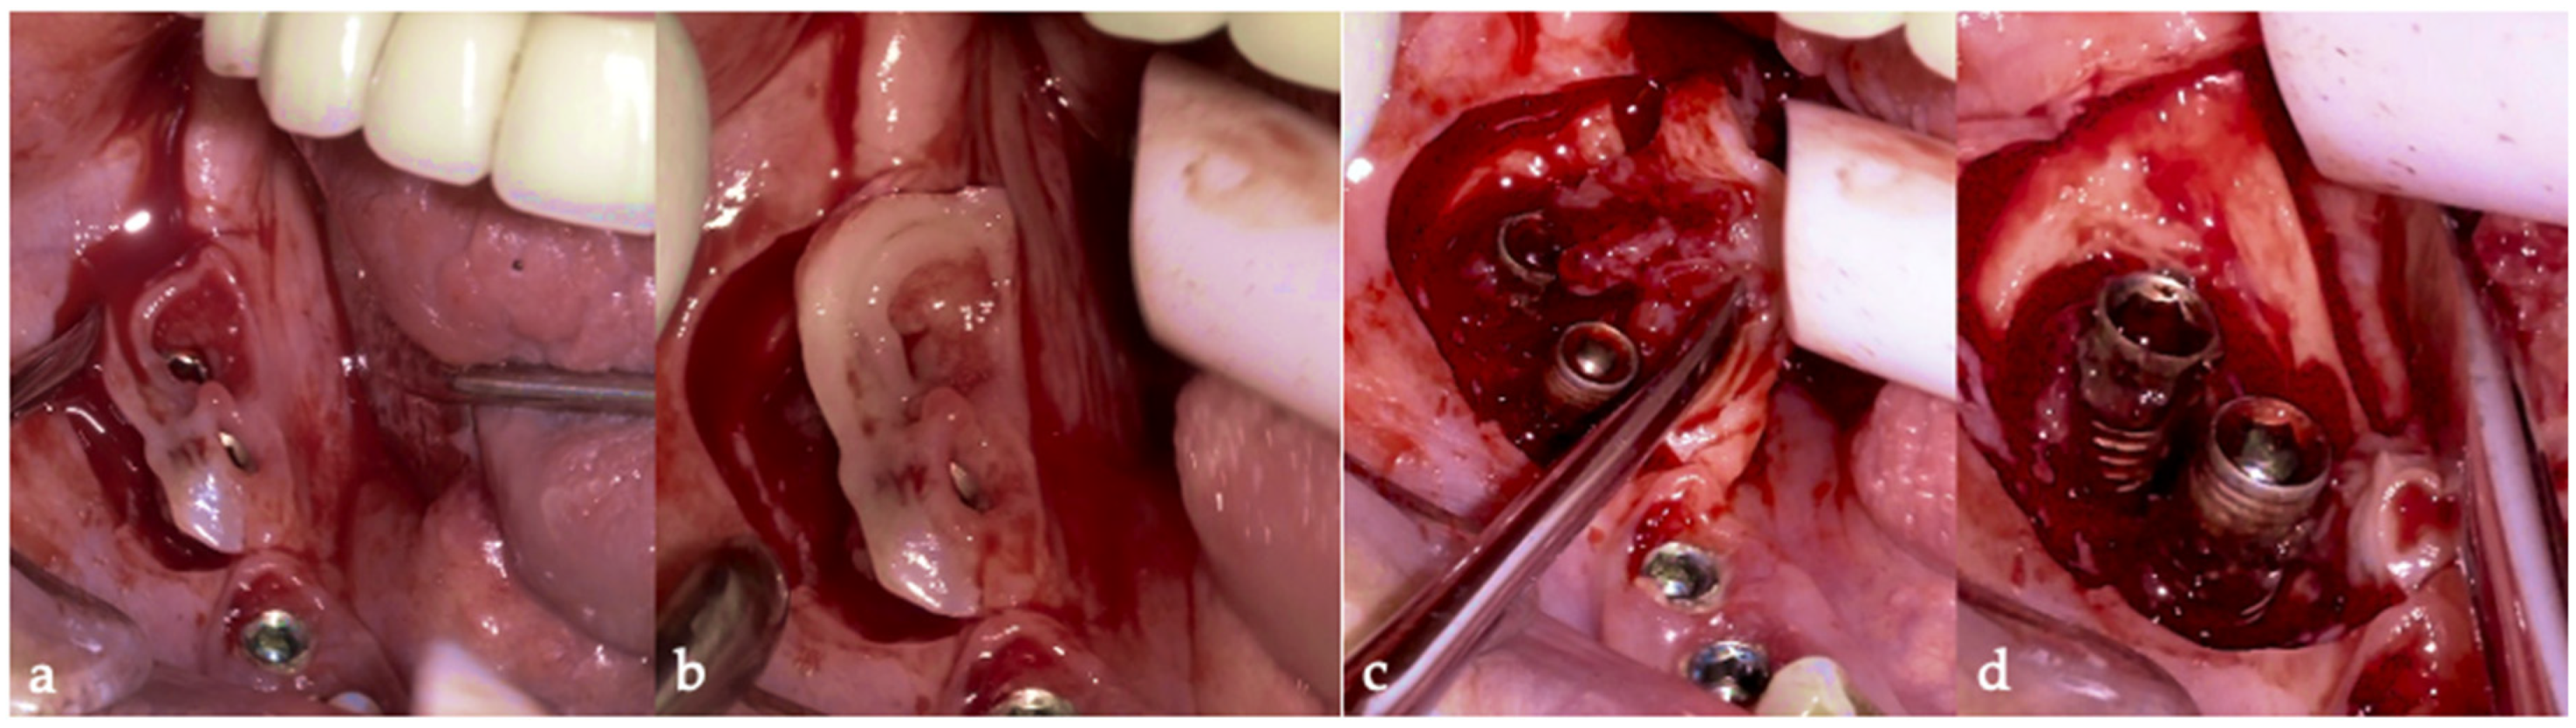

The same protocol mentioned above was used. A five-day antibiotic regimen was administered prior to the surgical procedure. At the surgery, the site had no suppuration and minimal BoP; the implants #33, #36, #37, #44, and #47 were removed, and new implants were placed to provide a new rehabilitation. For the site #41 (without mobility and severe bone loss), following prosthesis and abutment removal (Figure 17a,b), a BSF with two crestal extensions was made around the implants (Figure 17c,d), facilitating optimal access and flap management during the surgical procedure, eliminating the need to retract two flaps, as a midcrestal flap requires. The flap was retracted lingually; the granulation tissue was removed, and the contaminated implant surface fully exposed (Figure 17d).

The specialized “pin” guide was attached to the implant and contacts in juxtaposition with the surface of the implant–abutment connection platform (Figure 17e,f). The guide, extending the long axis of the implant, was used to position and control the iMPACT device’s rotational movement (Figure 17g,h), with cutting blades extended to maximum capacity (Figure 17h,i). Initial rotation levels of the alveolar bone (Figure 17j,k) permitted controlled mechanical injury to the bone, initiating the bone healing response, known as “Bone Regeneration Induction,” which is the second principle of the “Quadrant protocol.” Incremental machining at speeds between 200–300 RPM with torque settings of 7–9 N·cm removed contaminated implant threads (Figure 17l). The cutting action of the iMPACT prevents heating during manipulation, and the suction airflow removes macroparticles without the need for irrigation; thus, producing macro-sized particles removed via suction. The non-irrigation approach established an oxidative environment conducive to passivation layer formation. Post-machining (Figure 17l), the site was thoroughly cleaned and dried, and bleeding was stimulated and associated with the bone particulate graft (Figure 17m). The flap was repositioned, and abutments were placed back to keep and hold it in position for the final suture (Figure 17n). Antibiotics were continued postoperatively for three additional days.

Figure 17. Step-by-step treatment for peri-implantitis using the iMPACT and Quadrant protocol. (a) Initial clinical evaluation; (b) Removing the abutments for peri-implantitis treatment; (c,d) BSF raised for implant exposition; (e) Insertion of the hinge (pin), which was crewed into the implant; (f) Hinge in position; (g,h) iMPACT adapted to the hinge; (i) iMPACT spinning for implantoplasty; (j) The implant surface was smoothed, and bone around the implant was gently cut (osteotomy); (k) occlusal view showing the osteotomy; (l) implantoplasty finished—implant surface is completely smoothed (machined); (m) Bone graft; (n) Suture and abutments were repositioned.